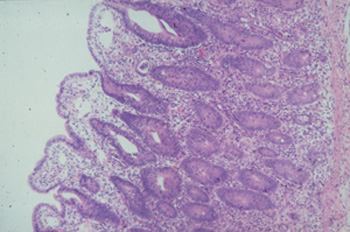

Picture 5.2.1 c (by J. Pohlenz)

Ileum of a healthy fattening pig with regular formation of intestinal villi and crypts, containing

a fair number of goblet cells (125x).